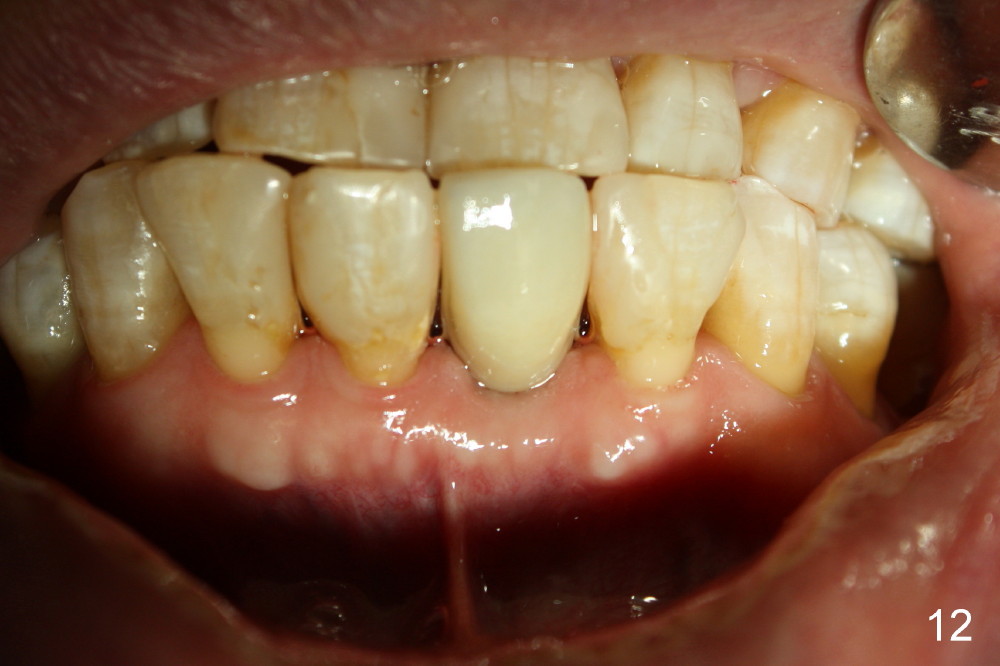

Fig.10,11 show 7 day follow up.  The permanent crown is seated 4.5 months postop (Fig.12).  Minimal bone resorption occurs at the crest 4 months postop (Fig.13), which is most likely associated with conservative approach (flapless).  The patient returns for follow up 2.5 months post cementation (Fig.14,15).  The implant remains in the bone 4 years post cementation (Fig.16 CT coronal section; lingual thread exposure, corresponding to preop defect in Fig.1).   There is mild coronal bone resorption 5 years 4 months post cementation (Fig.17).